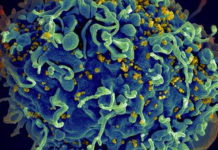

Anteriormente, los científicos en Alemania descubrieron que la transmisión del VIH está relacionada con la presencia de un amiloide fibrilar en el semen. Este fibrilar – una pequeña estructura, con carga positiva derivada de una proteína más grande – promueve la infección por VIH, ayudando a los virus encuentran y se unen a su objetivo: T CD4 células blancas de la sangre. En la edición de mañana de Cell Host & Microbe, los investigadores en el laboratorio de Warner C. Greene, MD, PhD, director de investigación de virología y la inmunología en Gladstone, describe un segundo tipo de fibrillas, que también tiene esta capacidad.

La transmisión sexual es para la inmensa mayoría de las infecciones por el VIH, y el semen es el modo de clave del virus de transporte. Estudios anteriores realizados por los Dres. Roan y Greene revela el mecanismo por el cual una carga positiva fibrilar en el semen – llamada SEVI – atrae el VIH como un imán, la unión a la carga negativa del VIH y ayudar a infectar a las células T CD4. En este caso, se dedicaron a investigar si los otros componentes del semen también jugó un papel.

En experimentos de laboratorio sobre muestras de semen humano, se identificó un segundo grupo de fibrillas -derivados de las grandes proteínas llamadas semenogelins – que mejoran la infección por el VIH así como SEVIhace. La eliminación de estos y otros componentes de carga positiva del semen disminuye la capacidad del VIHpara infectar las células T CD4 de sangre blancas. Lo que confirma el papel de estas fibrillas en la promoción dela infección por